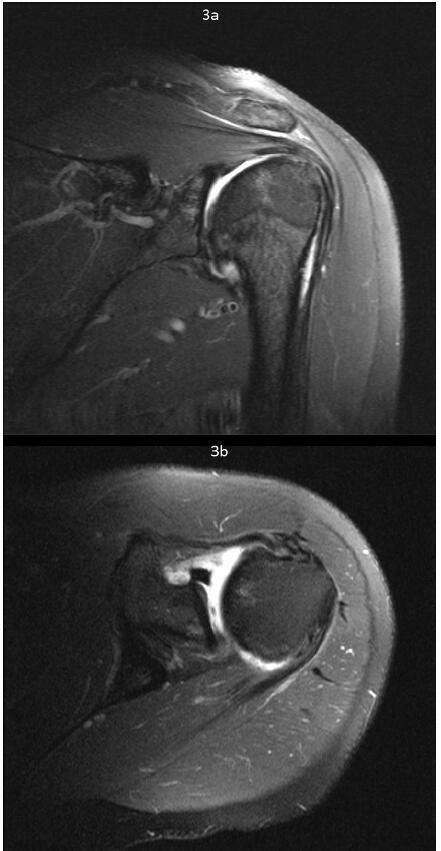

肩关节粘连性囊炎(AC)是一种常见的疾病,通常以临床病程延长和患者发病率高为特征,导致较高的社会经济负担。尽管有许多研究评估了各种治疗方式,但优化的治疗算法仍然难以捉摸。类似地,肩关节骨性关节炎(OA)表现出类似的临床和甚至更高的社会经济影响。诊断成像和短期疼痛管理方法的进步尚未产生有效的长期疾病改善疗法。随着肩关节骨性关节炎患者平均年龄的下降,人们对旨在减轻症状、提高生活质量和可能推迟侵入性手术干预的再生治疗越来越感兴趣。本文概述了AC和盂肱骨关节炎(GHOA)的病理生理学,并附有回顾性试点案例研究,证明了一种称为RELIEF®治疗的新型骨科方法的有效性。这种创新的方法产生了有希望的短期结果,包括治疗后6个月时多平面肩关节活动度(ROM)和功能评分的显著改善。RELIEF®治疗包括诊断性动态超声,以识别筋膜中的瘢痕或异常,并结合使用冷冻保存的微细化人羊膜悬浮液异体移植物(hAMA)和Isolyte晶体IV液的水解剖技术。在超声直接引导下,使用局麻药(2%利多卡因加肾上腺素1:20万)进行多次注射,目的是溶解纤维化瘢痕组织并将同种异体移植物输送到患处。治疗前和治疗后ROM评估由有执照的物理治疗师使用角度计进行。测量分别在基线(治疗前)和治疗后2周、2个月、4个月和6个月进行。此外,记录美国肩肘外科医生(American Shoulder and肘部外科医生)评分和视觉模拟量表(visual analogue scale, VAS)疼痛评分。随后在第二次RELIEF®治疗后4个月进行肩部MRI(无造影剂),以评估任何放射学上的显著变化,并将这些发现与患者报告的症状和整体功能状态的变化联系起来。

Adhesive capsulitis (AC) of the shoulder is a prevalent condition often characterized by a prolonged clinical course and significant patient morbidity, leading to a high socioeconomic burden. Despite numerous studies evaluating various treatment modalities, an optimized treatment algorithm remains elusive. Similarly, osteoarthritis (OA) of the shoulder presents a comparable clinical and an even higher socioeconomic impact. Advances in diagnostic imaging and short-term pain management options have not yielded effective long-term disease-modifying therapies. With the decreasing average age of patients suffering from glenohumeral OA, there is a growing interest in regenerative treatments aimed at alleviating symptoms, enhancing quality of life, and potentially postponing invasive surgical interventions. This paper provides an overview of the pathophysiology of both AC and glenohumeral osteoarthritis (GHOA), accompanied by a retrospective pilot case study demonstrating the efficacy of a novel orthobiologic approach known as the RELIEF® treatment. This innovative approach yielded promising short-term outcomes, including significantly improved multi-planar shoulder range of motion (ROM) and functional scores at six months post-treatment. The RELIEF® treatment involves diagnostic dynamic ultrasound to identify scarring or abnormalities in the fascia together with a hydrodissection technique using a combination of cryopreserved micronized human amniotic membrane suspension allograft (hAMA) and Isolyte crystalloid IV fluid. Under direct ultrasound guidance, local anesthetic (2% lidocaine with epinephrine 1:200,000) is utilized to perform multiple injections aimed at lysing fibrotic scar tissue and delivering the allograft to affected areas. Pre- and post-treatment assessments of ROM were conducted by a licensed physical therapist utilizing a goniometer. Measurements were taken at baseline (before treatment) and subsequently at two weeks, two months, four months, and six months post-treatment. Additionally, American Shoulder and Elbow Surgeons (ASES) scores and visual analog scale (VAS) pain ratings were recorded. An MRI of the shoulder (without contrast) was subsequently performed 4 months following the second RELIEF® treatment to evaluate for any radiographically significant changes and to correlate these findings with change in patient-reported symptoms and overall functional status.